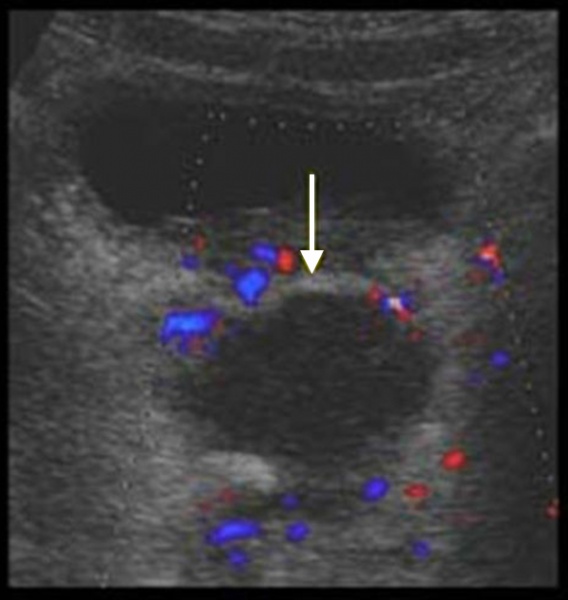

(Справа) Трансвагинальная цветовая допплерография в коронарной плоскости: многокамерный тубоовариальный абсцесс с детритом и окружающей гиперемией.